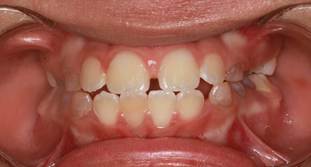

Figura 4. Análisis intraoral

Al examen intraoral se observa una mordida borde a borde de los incisivos antagonistas. La línea media dental inferior está desviada 1mm hacia la derecha. Piezas deciduas con signos clínicos de amelogénesis imperfecta.